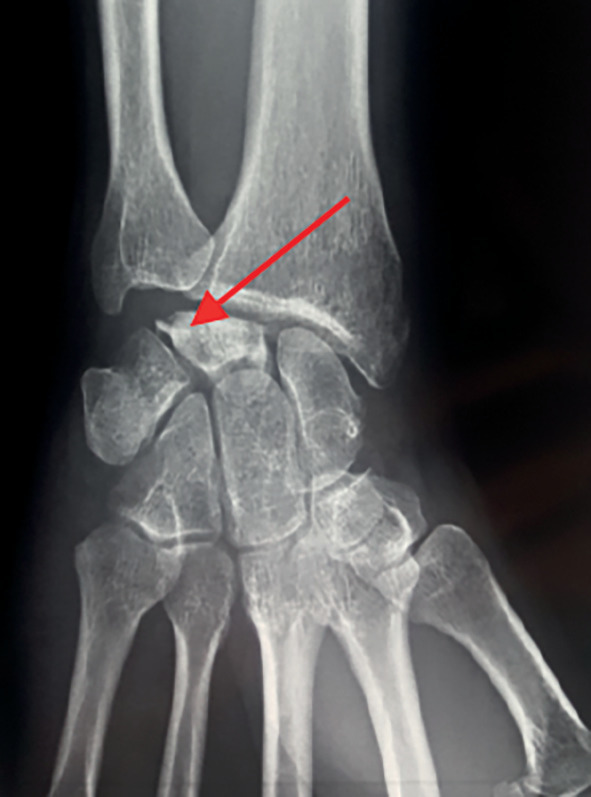

La radiographie montre une fragmentation partielle de cet os avec compactage osseux (fig. 1).

La maladie de Kienböck est une affection rare correspondant à une nécrose (dévitalisation) d’un des 8 os du carpe : le lunatum (fig. 2). On parle aussi de nécrose aseptique du semi-lunaire ou encore lunatomalacie. Cette pathologie atteint plus souvent les hommes (7/1) âgés de 20 à 40 ans.